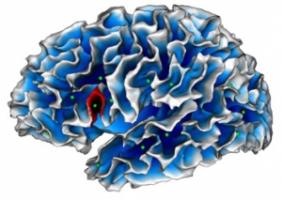

AUTISME: Un nouveau biomarqueur enfoui dans un pli du cortex